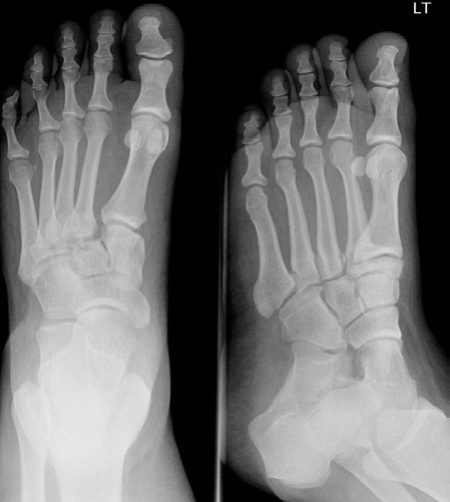

Minutes 1 and 2 EXAMINER : A 49-year-old lady fell on the stairs. Her foot is very painful, bruised, swollen and she can’t bear weight. The CT1 went to see her in A&E, but he is not sure what the problem is, what do you think? (Figure 8.3.) CANDIDATE : AP and oblique radiographs of left foot. There is diastasis of > 2 mm between the base of the first and second metatarsals, features suggestive of Lisfranc tarsometatarsal fracture dislocation. There is a small avulsed fragment of bone in that interval. This avulsion fracture could be from the insertion of the Lisfranc ligament into the base of the second metatarsal, called a ‘fleck sign’. [Always ask for the lateral radiograph.] EXAMINER : Okay, how will you manage this patient? CANDIDATE : I would start with assessing the patient as a whole, following ATLS protocol. I would take relevant history: mechanism of injury, patient’s general condition, past medical history, allergies, smoking as well as occupation and previous level of activity.

Figure 8.3 Anteroposterior (AP) and oblique radiographs left foot.